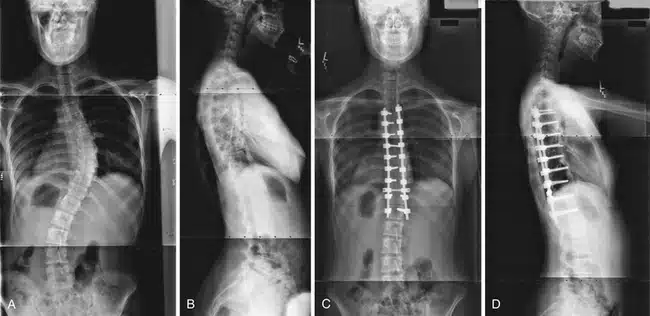

يمكن أن يحدث تضيق القناة لعدة أسباب. وأكثر سببين شيوعاً هما الشيخوخة والتهاب المفاصل. ويعود السبب في حدوث التهاب المفاصل إلى تلف الغضاريف، أو تطعيم العظام أو فرط نمو العظام. مع تقدم الإنسان بالعمر ، يتعرض جسم الإنسان لبعض العمليات التنكسية ، وقد تصبح الأنسجة في العمود الفقري أكثر سمكاً، وتنمو العظام بشكل أكبر من حجمها الطبيعي ، مما يشكل ضغطاً على الأعصاب. ويمكن أن تؤدي الشيخوخة أيضاً إلى حالات أخرى مثل الفُصَالٌ العَظْمِيّ (هشاشة العظام) والتهاب المفاصل الروماتويدي ، وكلاهما حالة التهابية يمكن أن تؤدي إلى تضيق القناة. يمكن أن يؤدي هشاشة العظام إلى حدوث تغييرات في القرص الفقري، وسماكة أربطة العمود الفقري ، وفرط نمو العظام، حيث تسبب هذه الحالات ضغطاً على الحبل الشوكي والأعصاب. ويمكن لأسباب أخرى بالإضافة إلى العمر والتهاب المفاصل ، أن تسبب تضيق القناة ومن هذه الأسباب ( العيوب الخلقية، انحناء العمود الفقري ، الجنف وأورام العظام ) بالإضافة إلى الأسباب المحتملة الأخرى مثل حدوث بعض الإصابات التي قد تسبب كسور أو التهاب في العمود الفقري أو بروز الأقراص الفقرية.

يعتمد علاج التضيق الشوكي على موقع التضيق وشدة العلامات والأعراض التي تشعر بها. تحدث مع طبيبك بشأن العلاج الأفضل لحالتك. إذا كنت لا تعاني من أعراض شديدة أو كنت لا تعاني من أي أعراض على الإطلاق، فقد يراقب طبيبك حالتك من خلال مواعيد متابعة منتظمة. قد يشير عليك طبيبك ببعض النصائح التي يمكن من خلالها الاعتناء بنفسك في البيت. إذا لم تساعد هذه النصائح، فقد يوصيك الطبيب بتناول الأدوية أو ممارسة العلاج الطبيعي. قد يكون التدخل الجراحي خياراً إذا لم تساعد العلاجات الأخرى. تتضمن أهداف الجراحة تخفيف الضغط على الحبل الشوكي أو جذور الأعصاب من خلال إنشاء مساحة أكبر داخل القناة الشوكية. وتتضمن أمثلة الإجراءات الجراحية لعلاج تضيق القناة الشوكية ما يلي:

مُعظم الأشخاص المصابين بالتضيُّق الشوكي هم فوق سِنِّ 50. على الرغم من أن التغيُّرات الانتكاسية يمكن أن تسبب تضيُّق العمود الفقري لدى الشباب، إلَّا أَّن هناك أسباباً أخرى يجِب أخذُها في الاعتبار. وتشمل هذه الأسباب: الإصابة، تشوُّهات العمود الفقري الخِلقية مثل الجنف، والأمراض الوراثية التي تؤثر على نموِّ العظام والعضلات في جميع أنحاء الجسم. يمكن أن يُميز التصوير الفقاري هذه الأسباب.